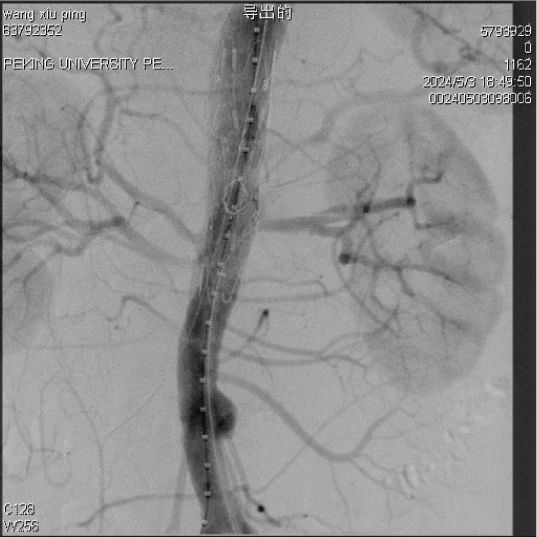

åˆåŠ›å¥è¡Œï¼Œç™¾ç‚¼æˆé‡‘。北京åå’ŒåŒ»é™¢è¡€ç®¡è¡¨ç§‘å›¢é˜Ÿåœ¨éƒ‘æœˆå®æ•™æŽˆæºå¸¦ä¸‹ï¼Œæ°é€¢å和建院101å‘¨å¹´ï¼Œå·²ç»æˆåŠŸåˆ©ç”¨ä¿„ç½—æ–¯è´µå®¾ä¼šé›†å›¢G-iliac创新IBD髂动脉分支支架,实现101ä¾‹é«‚å†…åŠ¨è„‰æ²‰å»ºç—…ä¾‹ã€‚ç™¾ä¾‹å¤æ‚病例的æˆåŠŸåŒ»æ²»ï¼Œå±•ç¤ºäº†åå’ŒåŒ»é™¢è¡€ç®¡è¡¨ç§‘å›¢é˜Ÿæ·±åŽšçš„å¦æœ¯åŸºç¡€å’Œé«˜æ˜Žçš„æ‰‹æœ¯æŠ€è‰ºï¼ŒåŒæ—¶ä¹Ÿæ‰¹æ³¨ï¼Œä¿„罗斯贵宾会集团G-iliac创新IBDé«‚åŠ¨è„‰åˆ†æ”¯æ”¯æž¶åœ¨é«‚å†…åŠ¨è„‰æ²‰å»ºæ‹¥æœ‰æ˜¾è‘—ä¼˜åŠ¿ï¼Œæ˜¯ç›®å‰æœ€æ¢¦æƒ³çš„解决规划。

北京å和医院在IBDï¼ˆé«‚åŠ¨è„‰åˆ†æ”¯æ”¯æž¶ï¼‰æŠ€æœ¯çš„åˆ©ç”¨ä¸Šå †é›†äº†ä¸°ç¡•çš„ç»éªŒã€‚åŒ»é™¢å·²ç»æˆåŠŸåœ°å°†é¦–æ¬¾åˆ¶å“化IBD支架G-iliac利用于101例患者,这些病例蕴å«è…¹è‡ªåŠ¨è„‰ç˜¤å½’å¹¶é«‚æ€»åŠ¨è„‰ç˜¤ã€å•纯髂总动脉瘤以åŠEVAR术åŽé«‚åŠ¨è„‰æ‰©å¼ çš„ç—…å˜ã€‚在这些病例ä¸ï¼Œæ²‰å»ºå•侧髂内动脉89例,沉建åŒä¾§é«‚内动脉12例,手术的å³åˆ»æˆåŠŸçŽ‡è¾¾100%,髂内动脉畅达率为97.3%。郑教授暗示,从å‰ä¸€å¹´ä¸IBDæŠ€æœ¯çš„åˆ©ç”¨èŽ·å¾—äº†ä»¤äººä¸æ„çš„æˆå°±ï¼Œæ‰‹æœ¯æˆåŠŸçŽ‡é«˜ï¼Œä¸”æ²¡æœ‰æœ¯ä¸å†…æ¼çš„产生。

俄罗斯贵宾会集团G-iliac支架æä¾›äº†ä¸¤ç§å…¥è·¯æ–¹å¼ï¼š1.肱动脉入路,它拥有挨次开释ã€ç»æµŽæ€§å¥½ã€æ˜“于超选髂内动脉蹬ç€ç‚¹ã€‚åŒæ—¶ï¼ŒæŠ€æœ¯é€‚应性高,在长鞘长度ä¸å®žæ—¶ï¼ŒSilverFlow髂内支架系统ä»èƒ½ç²¾å‡†è¾“é€è‡³æŒ‡æ ‡é«‚内动脉。2. å½“ä¸Šè‚¢å…¥è·¯å› æ‰æ›²æˆ–关塞而难题时,能够选择使用Fustarå¯è°ƒå¼¯éž˜è¿›è¡Œç¿»å±±å…¥è·¯æ²‰å»ºé«‚内动脉。在该ä¸å¿ƒçš„101例患者ä¸ï¼Œæœ‰52.6%选å–翻山入路沉建髂内动脉,并通过ä¸ä¼‘的技术创新和改进,使其å˜å¾—è¶Šå‘精准和便æ·ã€‚